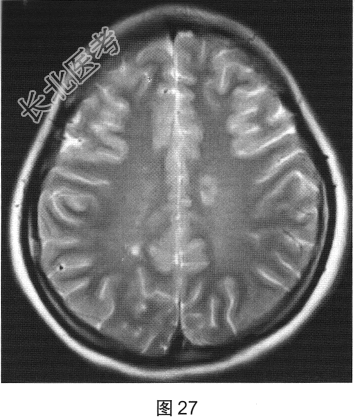

- [材料题] 患者女性,20岁,肢体无力2个月余。MRI检查结果如图27~图30所示。

- 多项选择题1.根据患者MRI平扫和增强的表现,其可能的诊断是( )

F、多发性硬化

- 多项选择题4.关于多发性硬化的诊断,叙述正确的是( )

A、“直角脱髓鞘征”是其较特征性的表现

B、脑内多发脱髓鞘病变

C、脊髓病灶多累及脊髓外周

D、病程呈复发.缓解交替

E、脊髓病灶多位于颈胸段脊髓

F、水肿及占位效应明显